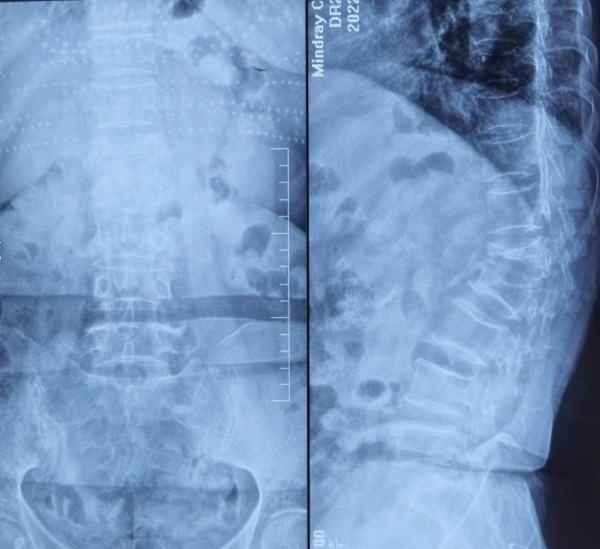

术前X线片可见后突角度23°

术后X线片可见后突角度12°